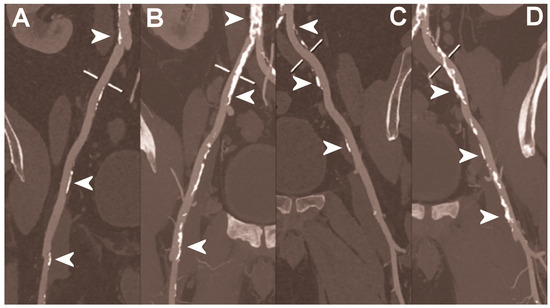

5.3. Abdominal Imaging

Figure 6.

Abdominal CT angiography using photon-counting computed tomography. The figure shows advanced multiplanar reconstructions without and with MIP algorithm of a distal abdominal aorta and ilio-femoral arterial axes derived from a photon-counting CT (Scanner: NAEOTOM Alpha, Siemens) acquisition (A,B right; C,D left). The projection start in the abdominal aorta carrefour and end in the right/left common femoral artery. There are massive calcifications along the common iliac arteries; however, both MPRs (A,C) and MIPs (B,D) are so sharply defining the edges of the structures that lumen assessment is not compromised (arrowheads).

Figure 7.

Abdominal CT angiography using photon-counting computed tomography. The figure shows advanced multiplanar reconstructions of an abdominal aorta and ilio-femoral arterial axes derived from a photon-counting CT (Scanner: NAEOTOM Alpha, Siemens) acquisition (A,B). In (A) the projection starts in the abdominal aorta at the level of thoraco-abdominal junction and ends in the right common femoral artery while in (B) it ends in the left common femoral artery. While there are significant calcifications along the vessels (arrowheads in A and B), the vessel wall is so sharp that the fact that there is no lumen reduction appears to be quite natural as compared to the common blooming effect seen with conventional energy-integrating detectors.